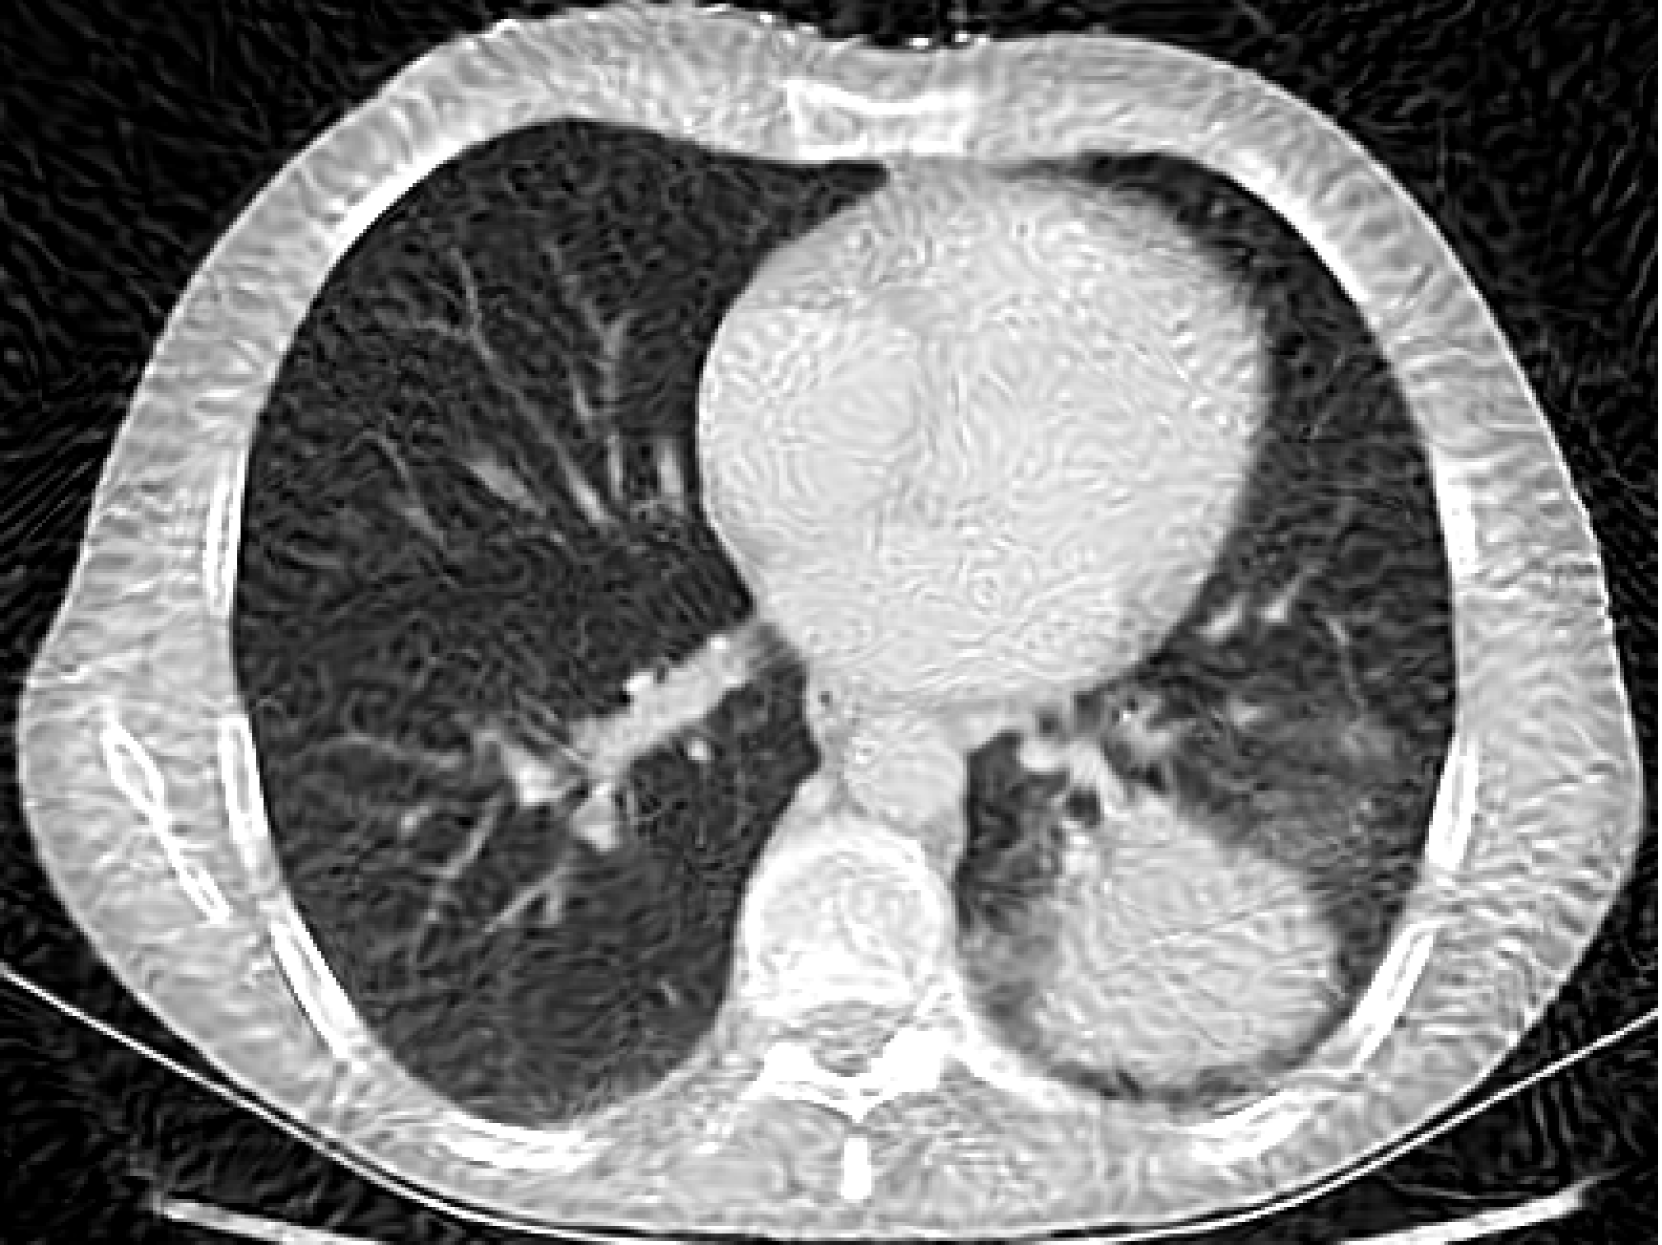

Figure 4: Experiments on computed tomography reconstruction with various INR architectures. We report average PSNR and standard error across five random trials.

5.1 Computed Tomography(CT) Reconstruction

In this experiment we simulated CT reconstruction by taking 100100100100 equally spaced CT measurements of a 326×435326435326\times 435326 × 435 chest X-ray image (Clark et al., 2013). Figure 4 shows the results compared to other INR architectures showing that our BW-ReLU neural networks perform just as well and perhaps slightly better than conventional INR architectures. Full experiment details can be found in Section D.1.